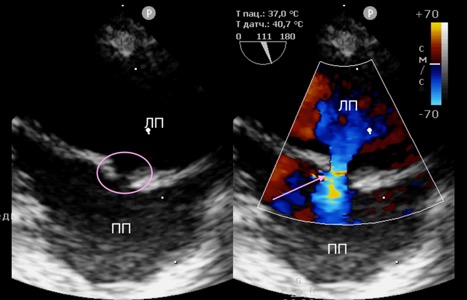

После достижения необходимой анестезии устанавливали интродьюсер, через который в правое предсердие вводился проводниковый катетер. Наведение проводника на межпредсердную перегородку осуществлялось под контролем чреспищеводной эхокардиографии. В большинстве случаев выбирали область овальной ямки (лат. fossa ovalis) как наиболее анатомически безопасную и предсказуемую зону для пункции. Пункция перегородки выполнялась обратной (тупой) стороной проводника, что снижало риск повреждения окружающих структур (рис. 2). После успешного проникновения в левое предсердие по проводнику заводился баллонный катетер (диаметром от 12 до 14 мм).

Объективным критерием успешности проведения процедуры являлось наличие сброса слева направо, подтвержденного методом цветного доплеровского сканирования(рис. 4), а также снижение давления в левом предсердии, которое оценивалось с помощью катетера, вводимого в левое предсердие. После завершения инсуффляции баллон и проводник удалялись, а сосуд ушивался непрерывным швом.